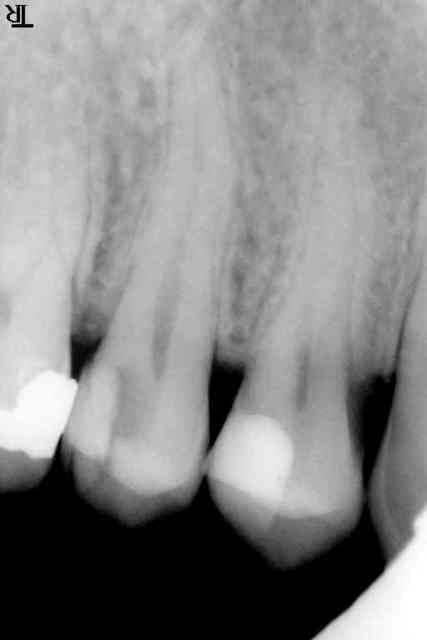

ça y est j'ai réussi !!!!!!!

Anesthésie tubérositaire haute + paraapicale haute au niveau de 14.

Encore une très légère sensation à l'ouverture donc j'ai rajouté une dose en intrapulpaire.

Enfin tout est bien qui finit bien.

Quant à l'aspect, ce n'était pas particulièrement inflammatoire. Je n'ai pas eu un saignement abondant. Je pense que le problème était vraiment un problème d'anesthésie. Une particularité anatomique ???

Toujours est-il ( je continue à avouer mes échecs ...) que ma séance précedente durant laquelle j'ai injecté, injecté et encore injecté m'a valu une nécrose en palatin. Cependant rien de catastrophique.